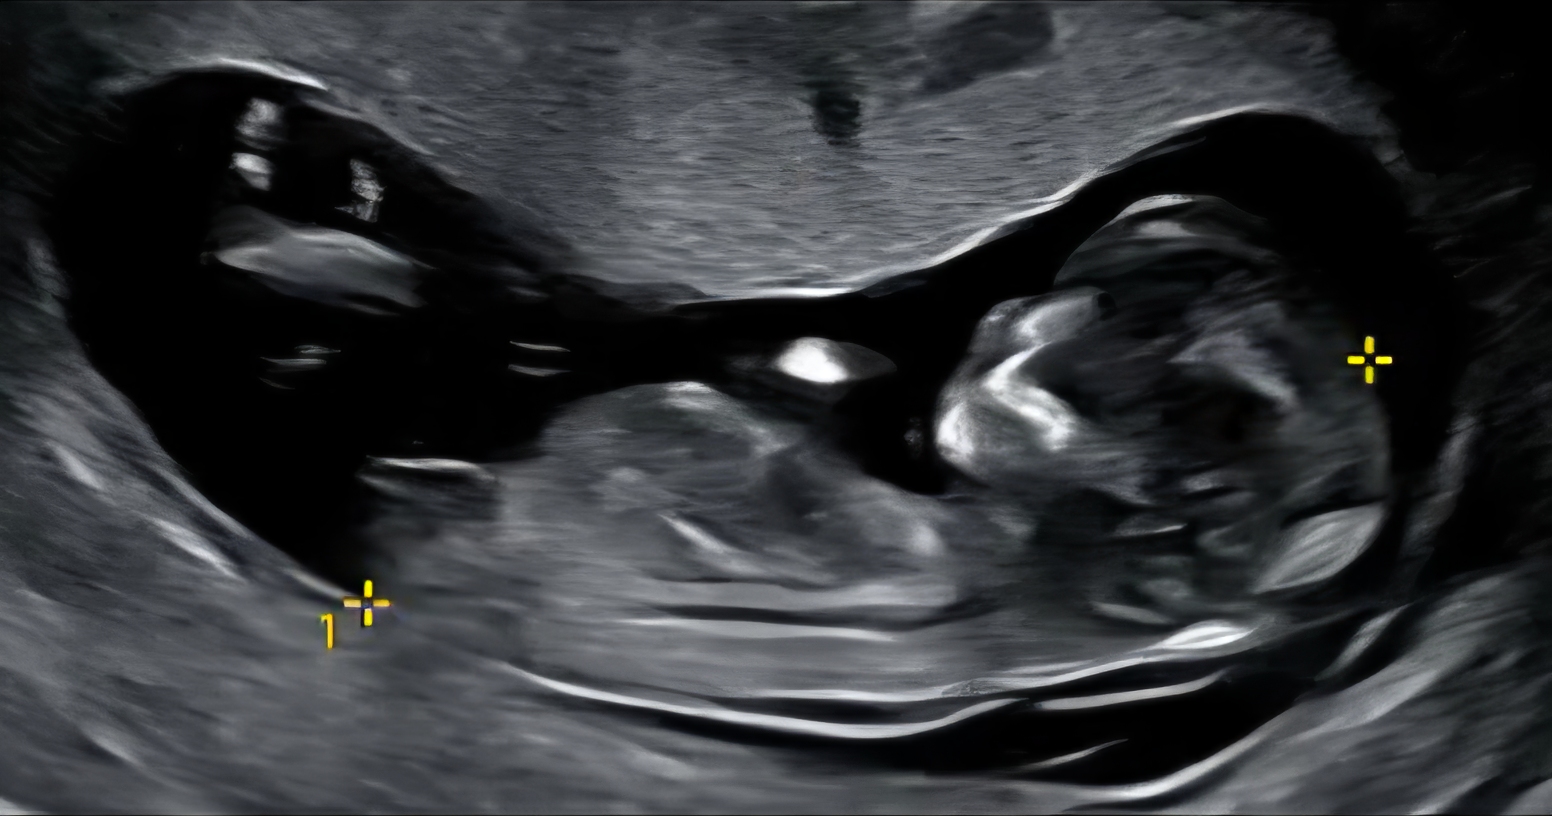

각도법 잘 보시는 분들 투표 부탁드려요..! 어제 니프티 검사하고 오긴했는데 너무 궁금하네요